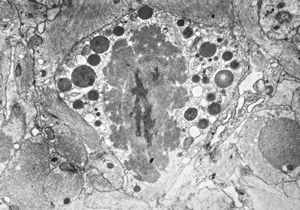

F,3y. | toxoplasmosis